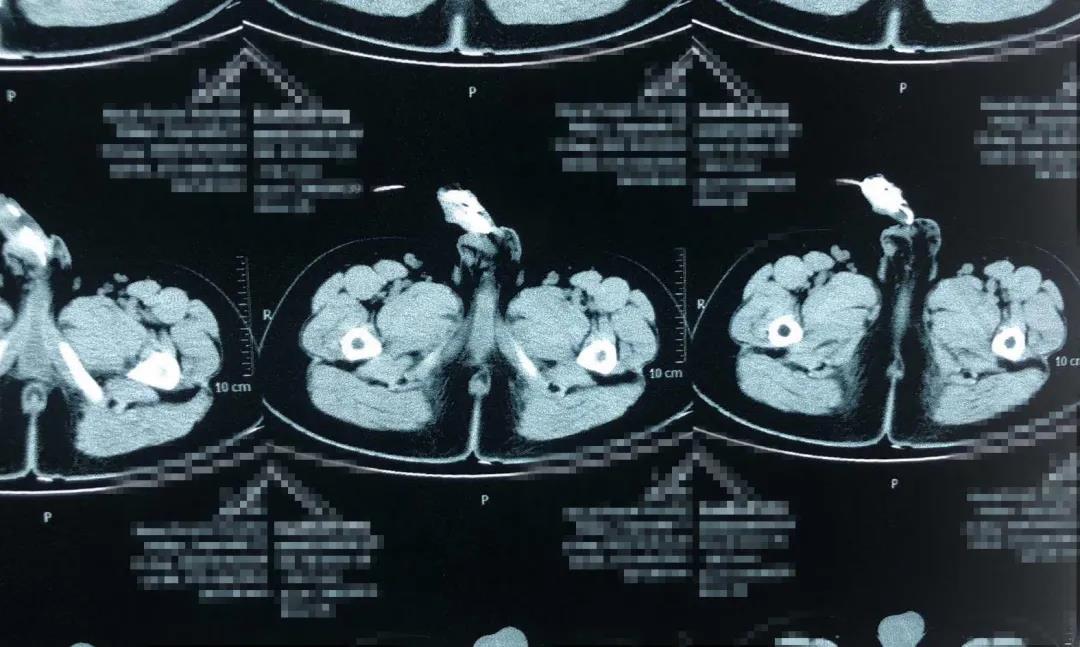

“CT以及泌尿系彩超檢查,發(fā)現(xiàn)血尿的原因可能是膀胱內(nèi)的這根電線異物引起的,且該異物在體內(nèi)出現(xiàn)重疊嵌頓,直接使用外力勢(shì)必會(huì)對(duì)患兒的尿道、生殖器甚至膀胱造成不可逆的損害。”副主任醫(yī)師劉太陽(yáng)說(shuō),及時(shí)手術(shù)取出是必須的,而手術(shù)方式的選擇成為患兒身體健康的重要環(huán)節(jié)。

“該異物一端深深插入膀胱肌層內(nèi),即將穿破膀胱進(jìn)入腹腔……”

完善術(shù)前檢查后,馬上進(jìn)行手術(shù)。以劉太陽(yáng)主刀、張奎為助手的手術(shù)團(tuán)隊(duì)先將患兒尿道口切開(kāi)2CM注入適量潤(rùn)滑劑后,對(duì)照各影像檢查結(jié)果,巧妙的將重疊嵌頓一段段舒展后,一段段取出。“整個(gè)異物長(zhǎng)度達(dá)50cm。”當(dāng)異物被完整取出后,劉太陽(yáng)和張奎再次通過(guò)輸尿管鏡對(duì)患兒尿道及膀胱進(jìn)行檢查,發(fā)現(xiàn)無(wú)異物殘留和明顯出血后,立即縫合,手術(shù)完成。